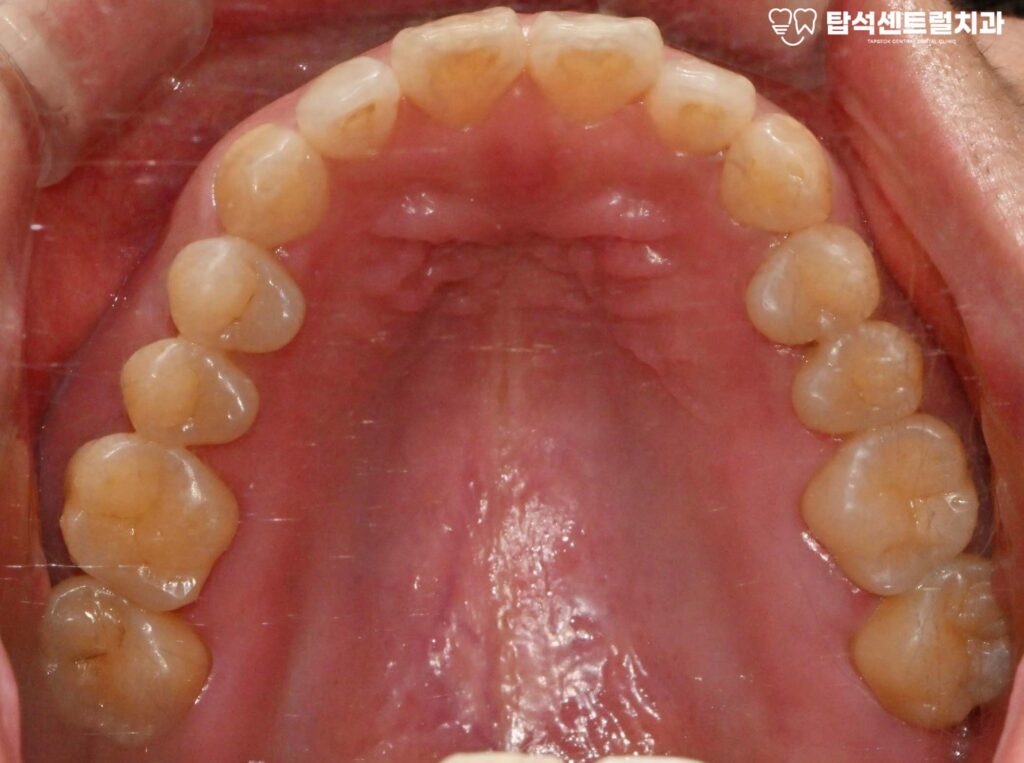

잇몸뼈의 상태를 확인한 모습입니다.

잇몸 뼈가 남아 있는 양에 따라,

뼈이식의 필요 유무가 정해집니다.

수술 후 일정 기간 동안

임플란트가 뼈와 단단히 결합하는

골유착 과정을 거치게 됩니다.